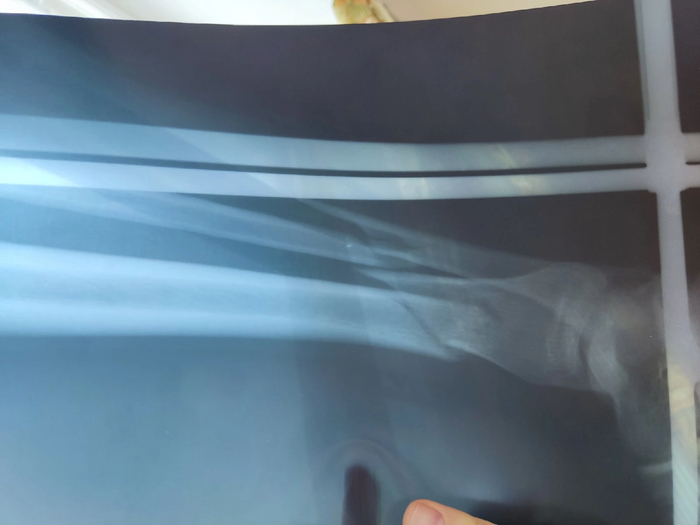

День 5. Удалось поспать +- часа четыре. Сегодня препятствием сна были эластичные бинты, которые мне намотали вчера на переломанную ногу. Сдавливало сильно и от этого вся икра гудела. Ощущения неприятные. Снимать их запретили, но про то, что нельзя ослабить, ничего не говорили. Поэтому кое-как дотянулся до больной ноги и ослабил сверху бинты. Дискомфортные ощущения прошли и удалось уснуть. Стандартное утро началось с укола в пузо и измерения температуры. К 10.20 пришёл врач и сообщил: "По результатам рентгена необходимо оперировать, так как кость лопнула и поперёк и вдоль. Но операция, дело добровольное, вы можете отказаться от неё".

День 6. "Завтра операция". Ночь была ужасной. После поездки на УЗИ и ощупывания ноги внутри её что-то произошло. Скорее всего осколок как-то неудачно встал и теперь при малейшем моём движении вызывал резкую боль. За эту ночь почти не спал, потому что лежал в одной позе, не шевелясь, дабы не заорать. Надеялся, что утром полегчает. Вчера ещё с меня перед УЗИ сняли эластичные бинты и должны были одеть заново. Медсестра сказала , что подойдёт по позже и намотает. Уже по традиции - никто не пришёл и в 16.00 заступила новая смена. При уколе в живот в 17.00, спросил про необходимость наматывания бинтов. Сказали : "Да, надо, но попозже". В 22.00 при уколе в живот снова напомнил про бинты, сказали: "Пусть утренняя смена занимается". И вот наступило утро 6 дня. Я, пролежавший неподвижно до утра, и надеясь, что хоть как-то получится вернуть какую-нибудь маневренность, был разочарован. Резкая боль при движении осталась. Пришёл доктор в 9.30 и спросил, заказал ли я пластину. Получив утвердительный ответ, поинтересовался, почему не забинтована нога. Ответил ему честно, что про меня забыли. Доктор ушел и пришла медсестра. Сказала, что вчера забегалась, и забыла намотать бинты. Начали пробовать их намотать, но вышло только на половину, так как я теперь не могу приподняться всё от той же острой боли при движении. Терпим. Доктор сказал, что возможно операция будет в четверг, то есть завтра, если получится выпросить операционную. Как я понял, здесь, в БСМП, есть график на операционную и по этому графику отделу травматологии можно пользоваться операционной в пятницу. Время 11.30 , пришёл доктор и сказал, что операция будет точно завтра, с утра ничего не кушать и не пить. Я готовился заранее и уже сутки не ел, чтобы больше не командовать своим судном. Медсестра принесла какие-то бумаги про переливание крови, добровольное вмешательство и прочее. Всё подписали, удалось получить снимок, теперь понятно какие осколки режут меня изнутри. Укололи последний укол в пузо и сказали, что дальше будет назначено другое лечение.

День 8. Спать получилось с 23.00 до 01.00 пока действовал промедол. И по одному часу после двух таблеток кеторола. С 4 часов я бодрствовал. С утра пришла медсестра, взяла кровь и вколола антибиотики. За ней пришёл доктор, спросил самочувствие. Повертел моей ногой со стороны в сторону. Боль терпимая и слышен хруст. На операции мне скрепили большую берцовую кость, а малую не трогали, так как за одну операцию это не делается. Сказал, будем наблюдать и возможно оперировать повторно. Попросил, чтобы привезли костыли, надо двигаться. Разрешил вставать и поворачивать ногу. Ура! Как только он ушёл из палаты, я, похрустывая малоберцовой костью, повернулся как смог на бок и меня отключило. Сказывалось количество недосыпа. Надо сказать, я всех родственников и друзей отговаривал что-либо мне привозить кроме воды и просил навещать пореже. Мне так было проще, а после армии я есть могу всё, поэтому спокойно ел только больничную еду. Через час я подскочил от грохота и слов - хватит уже спать, поехали на рентген. С коляской ворвался хороший человек Ваня. Я пытался ему объяснить спросонья, что доктор вроде не назначал, но Ваня победил. Он сказал , что узнал у медсестёр, что рентген мне нужен, но отвезти меня они не могут, так как очень заняты (при этом она листала ленту инстаграмма). Ваня выпросил коляску и свозил сам меня на рентген. Оказалось, ему тоже когда-то досталось, и он тут был более чем местный. Получили снимок и слегка приуныли, малоберцовая прилично оттошла в сторону. Посмотрим, что скажет доктор в понедельник. Сегодня я дембельнулся со своего судна, кое-как на костылях добрался до туалета. Маленькая победа. На завтра план побег на тихом часу домой, очень хочется помыться. Впереди выходные, думаю ничего кроме перевязок и антибиотиков со мной делать не будут. Жду понедельника.